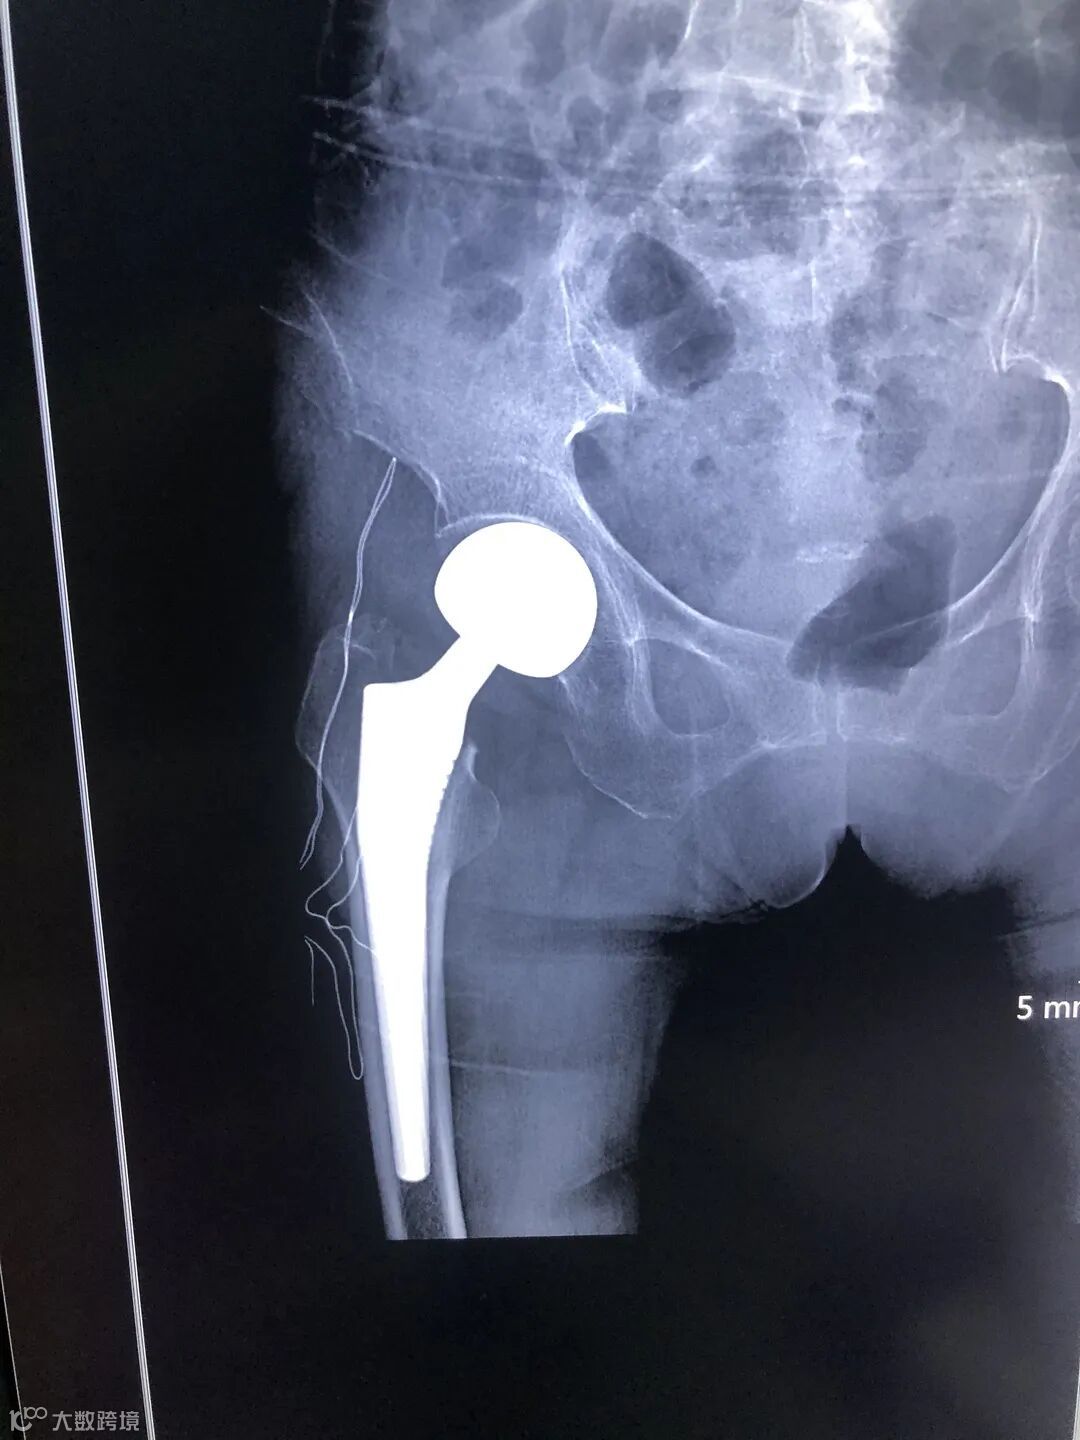

2月10日,疫情高峰,一位88岁高龄老太太,在家中不慎跌倒致右髋关节疼痛难忍,活动障碍,因疫情原因不敢来医院就诊,在家中卧床强忍2天,实在难以忍受来到我院。经过严格的流行病学及相关检查,发现右侧股骨颈骨折,新冠专家组排除新冠肺炎后收住外科,患者高龄,基础病多,如不手术,长期卧床死亡率极高,本着痛苦小、恢复快,早下地的理念,外科团队在入院第二天成功就实施了右侧人工髋关节置换术,手术前后只用1个小时,术后第一天便能坐起,第二天就开始下地活动,极大的减少了患者卧床痛苦和并发症。在我科医护人员的精心治疗下,目前老人已拆线顺利出院,出院时老人及家属连连道谢,感谢外科医护人员的细心照料,感谢技艺精湛的医护们挽救了她的生命,看着老人一家欢天喜地的回家,最开心的是每一名医护人员。

术后X片